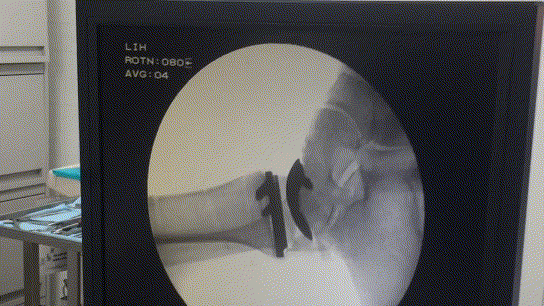

Интраоперационная проверка движений в суставе с помощью электронно-оптического перобразователя рентгеновских лучей.